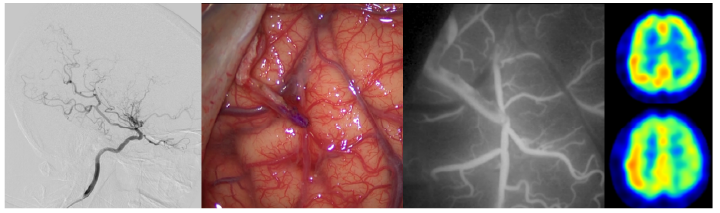

もやもや病は、わが国で初めて発見された原因不明の脳血管疾患であり、小児や若年成人における脳卒中の重要な原因の一つです。脳の主要な動脈である内頚動脈が、進行性に狭窄し、それを補うように異常な血管網が発達します。本疾患の診断および治療には高度な専門性が求められ、正確な画像診断や病態評価に基づく適切な治療戦略が重要となります。

当科は、国内でも有数のもやもや病の治療経験を有しており、小児・成人のいずれに対しても、直接血行再建と間接血行再建を組み合わせた複合血行再建術を一貫して行ってきました。脳梗塞や脳出血の再発予防に有効性である本手術を、長年にわたる臨床経験と研究に基づき安全に実施しています。さらに、もやもや病に特徴的な手術後の脳循環動態の変化を的確に評価し、きめ細かな周術期・術後管理を行うことで、手術合併症の予防に努め、安定した治療成績を維持しています。